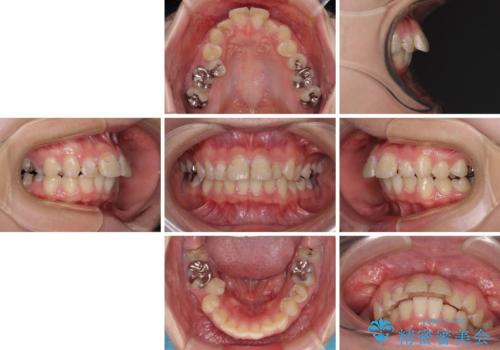

- 上の前歯の出っ歯とでこぼこの歯並びを気にして来院された患者様です。

上下顎歯列ともに前方に突出していましたが、上顎歯列がより前方位にあったため、上顎左右は第1小臼歯を、下顎左右は第二小臼歯を抜歯することとしました。

目立たないワイヤー装置にて抜歯矯正を行うこととしました。